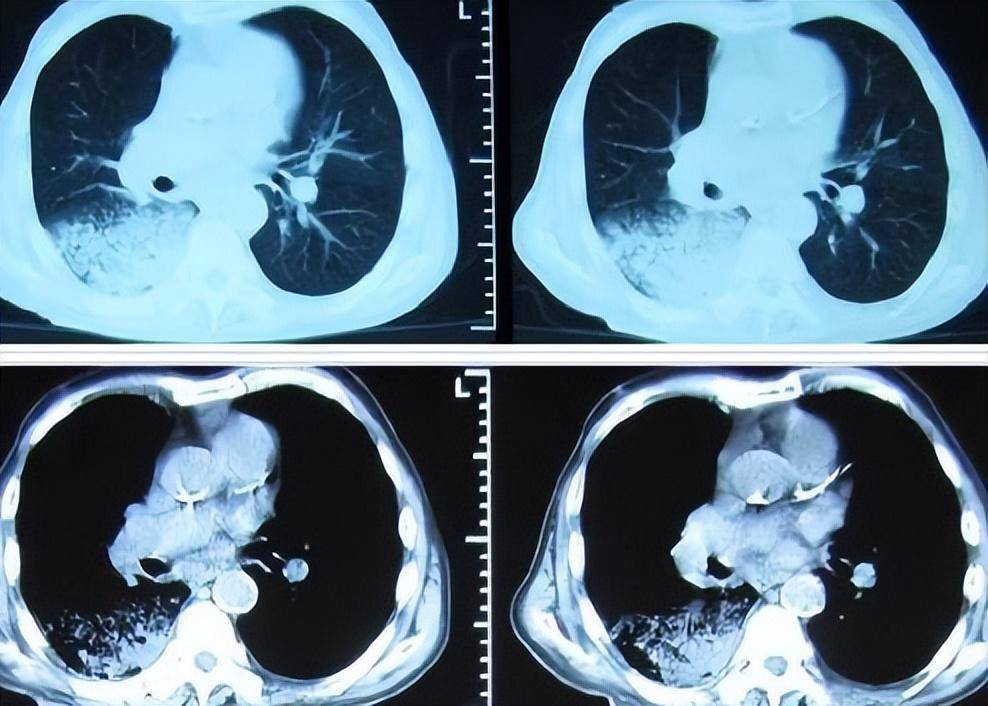

“白肺”,医学上称为急性呼吸窘迫综合征(ARDS),是一种严重的肺部疾病,当肺泡充满液体而不是氧气时,X光片上的肺部就会呈现出白色。这种病症通常由感染、创伤或其他疾病引起,它让我体验到了前所未有的呼吸困难。